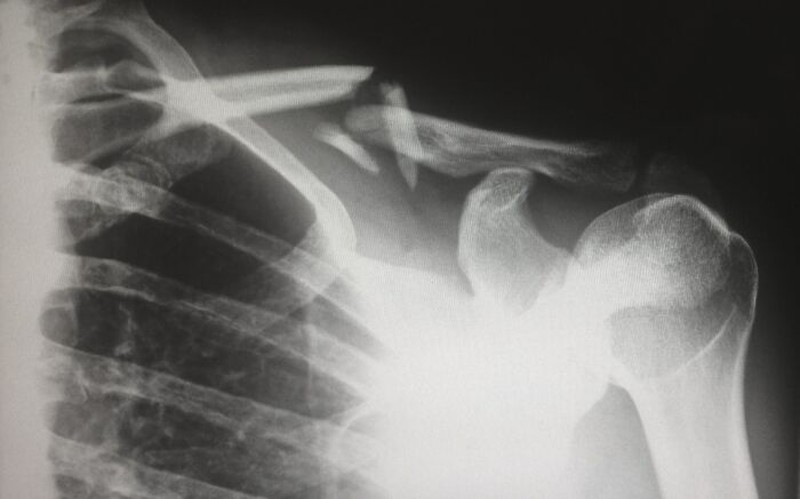

Ketika teknologi sinar-X pertama kali tersedia secara luas untuk dokter anak, mereka melihat sejumlah besar patah tulang yang mengejutkan. Ternyata terungkap banyak anak yang mengalami pelecehan dan kekerasan. Foto: Reddit via Bored Panda